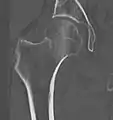

في الحالات التي يشتبه في وجود كسر الورك ولكنه ليس واضح على الأشعة السينية، الاشعة المقطعية ثلاثية الابعاد (3D reconstruction) تكون مفيده للتشخيص. وقد اكتسب التصوير بالرنين المغناطيسي أهمية في تشخيص الحالات الغامضه من كسور رقبة عظمة الفخذ. في غضون 24 ساعة يمكن للتغييرات أن تري في التصوير بالرنين المغناطيسي. مسح العظام هو أقل فائدة لأنه قد يستغرق ما يصل إلى الاسبوع لإظهار التغيرات وخاصة في كبار السن.

عنق عظمة الفخذ

كسور عنق الفخذ يحدث في العنق الضيق بين الرأس الدائريه لعظمة الفخذ وجسم العظمة. هذا الكسر في كثير من الأحيان يعطل وصول الدم إلى رأس عظم الفخذ.

لكن من المضاعفات الشائعة والخطيرة لكسر عنق الفخذ نخر الرأس (موت رأس العظمة نتيجة انقطاع الدم عنها) avascular necrosis والأوعية الدموية في الرأس تتأثر بسهولة أثناء كسور الفخذ أو تكون ورم أو انتفاخ داخل كبسولة المفصل. هذا يمكن أن يؤدي إلى خنق امدادات الدم إلى رأس الفخذ وموت العظام والغضاريف.

موت رأس عظمة الفخذ يحدث في كثير من الأحيان (20 ٪) في كسر عنق عظمة الفخذ، وذلك بسبب انقطاع الدم عنها. وهو أمر نادر بعد كسور ما بين النتوئين.